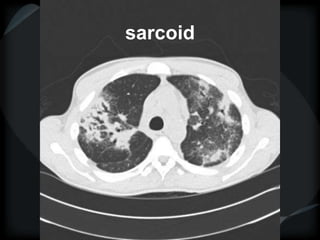

Sarcoid

perilymphatic